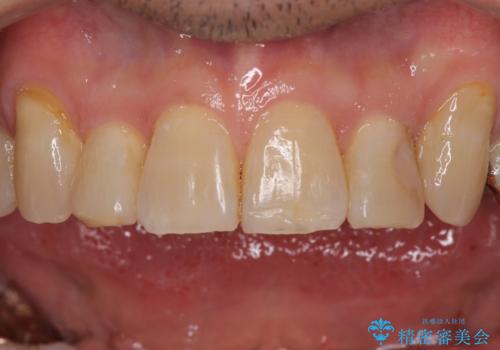

銀歯やむし歯治療されている歯を抜歯する治療計画としたため、やや時間はかかりましたが、治療後の仕上がりには大変満足していただけました。